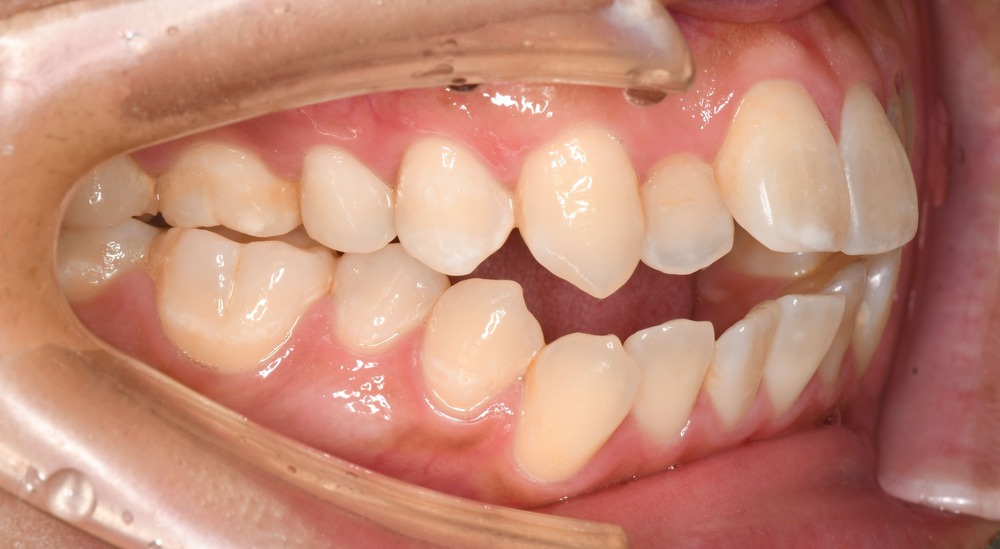

口腔内(右側)からは口ゴボ、反対咬合を確認

- 上下前歯の強い唇側傾斜が見られます。

- 大臼歯は反対咬合(クロスバイト)となっています。